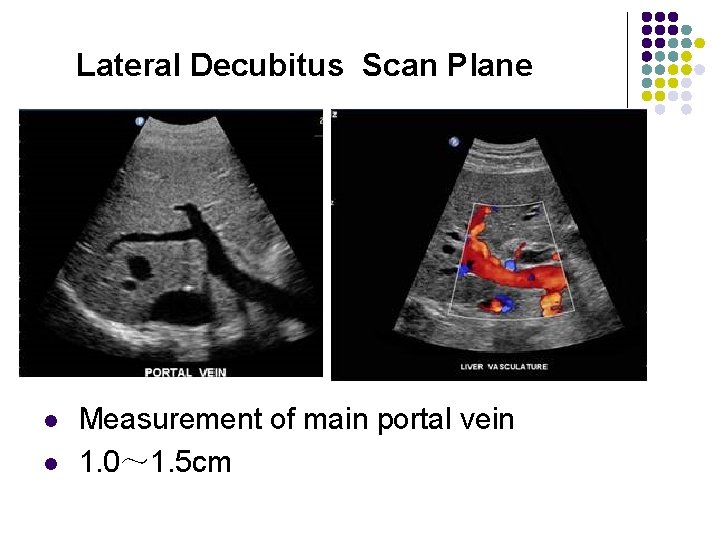

Lateral Decubitus Scan Plane l l Measurement of main portal vein 1. 0~ 1. 5 cm